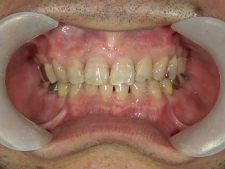

矯正歯科 治療後矯正歯科 全顎ワイヤー矯正 治療後矯正歯科(全顎ワイヤー矯正)治療後

矯正歯科 治療後 左上6番欠損のため、7番を6番の位置へ前方牽引

no.22_8175_治療後_右.jpgno.22_8175_治療後_正面.jpgno.22_8175_治療後_左.jpg